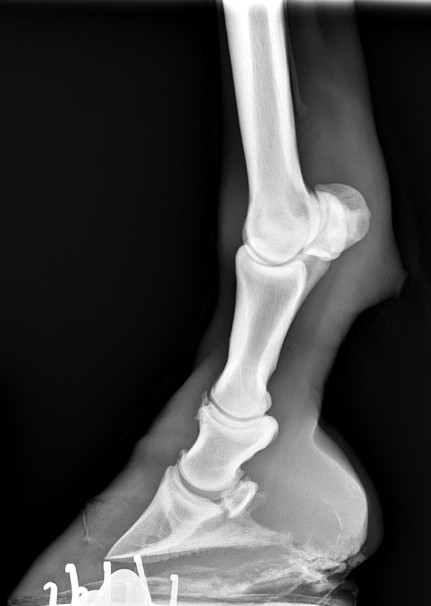

Создано устройство для позиционирования при рентгенографии копыт лошадей. Проводной DR-Рентген используется до и после перековки.